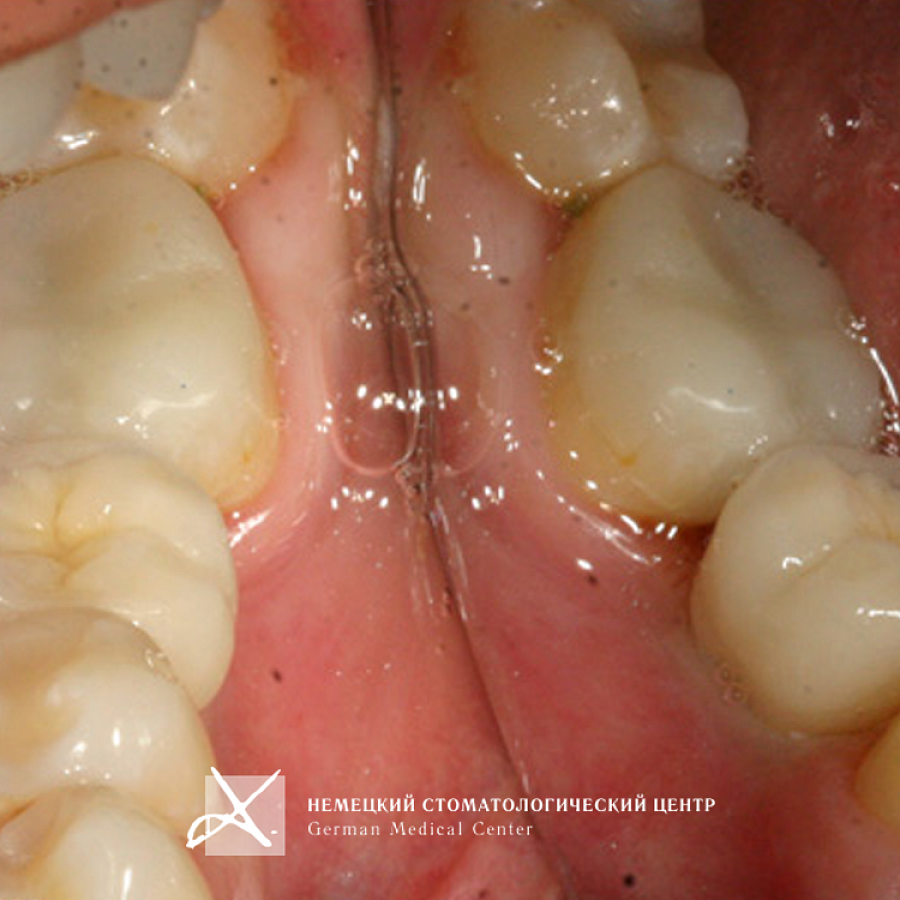

Обращение пациента

картинка

Пациентка обратилась с жалобой на отсутствие зуба 36.